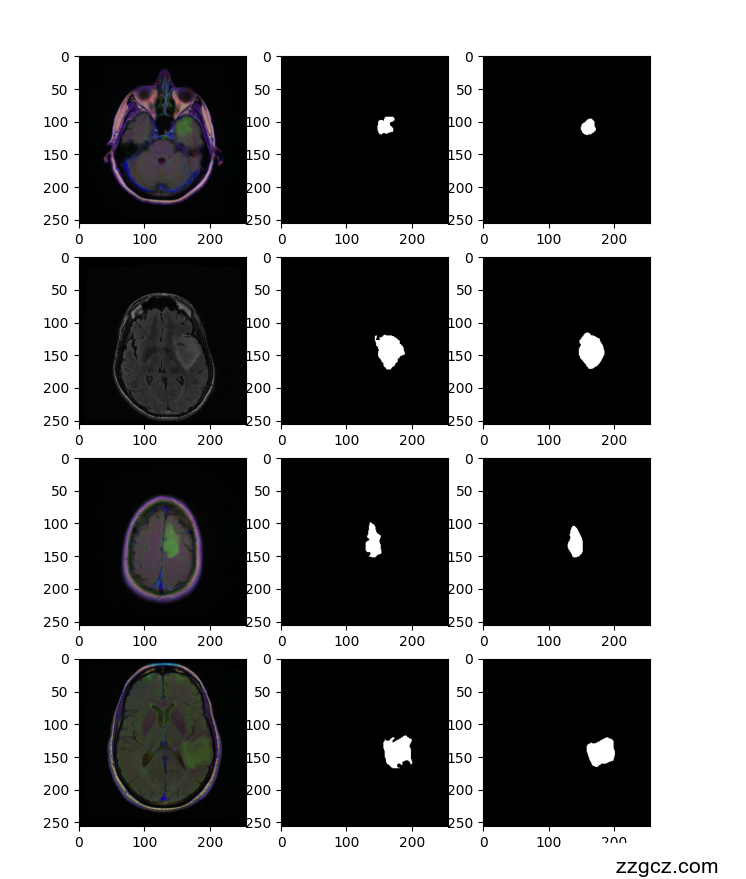

使用PyTorch框架和Segmentation Models PyTorch库实现的深度学习模型,旨在通过MRI图像进行脑部病变区域的分割。本模型使用了具有预训练权重的U-Net网络,进行图像分割任务的训练和评估。

(3) 模型定义

采用Unet网络架构,选择resnet34作为编码器,并初始化编码器权重为ImageNet上的预训练权重。模型输入通道设置为3(适用于RGB图像),输出通道设置为2,对应于图像的背景和病变区域。

3.3、模型运行结果

epoch: 0 loss: 0.039 accuracy: 0.827 IOU: 0.223 test_loss: 0.066 test_accuracy: 0.981 test_iou: 0.413

epoch: 1 loss: 0.016 accuracy: 0.983 IOU: 0.507 test_loss: 0.039 test_accuracy: 0.988 test_iou: 0.62

epoch: 2 loss: 0.01 accuracy: 0.989 IOU: 0.662 test_loss: 0.029 test_accuracy: 0.989 test_iou: 0.669

epoch: 3 loss: 0.008 accuracy: 0.99 IOU: 0.701 test_loss: 0.021 test_accuracy: 0.992 test_iou: 0.751

epoch: 4 loss: 0.006 accuracy: 0.991 IOU: 0.729 test_loss: 0.017 test_accuracy: 0.991 test_iou: 0.703